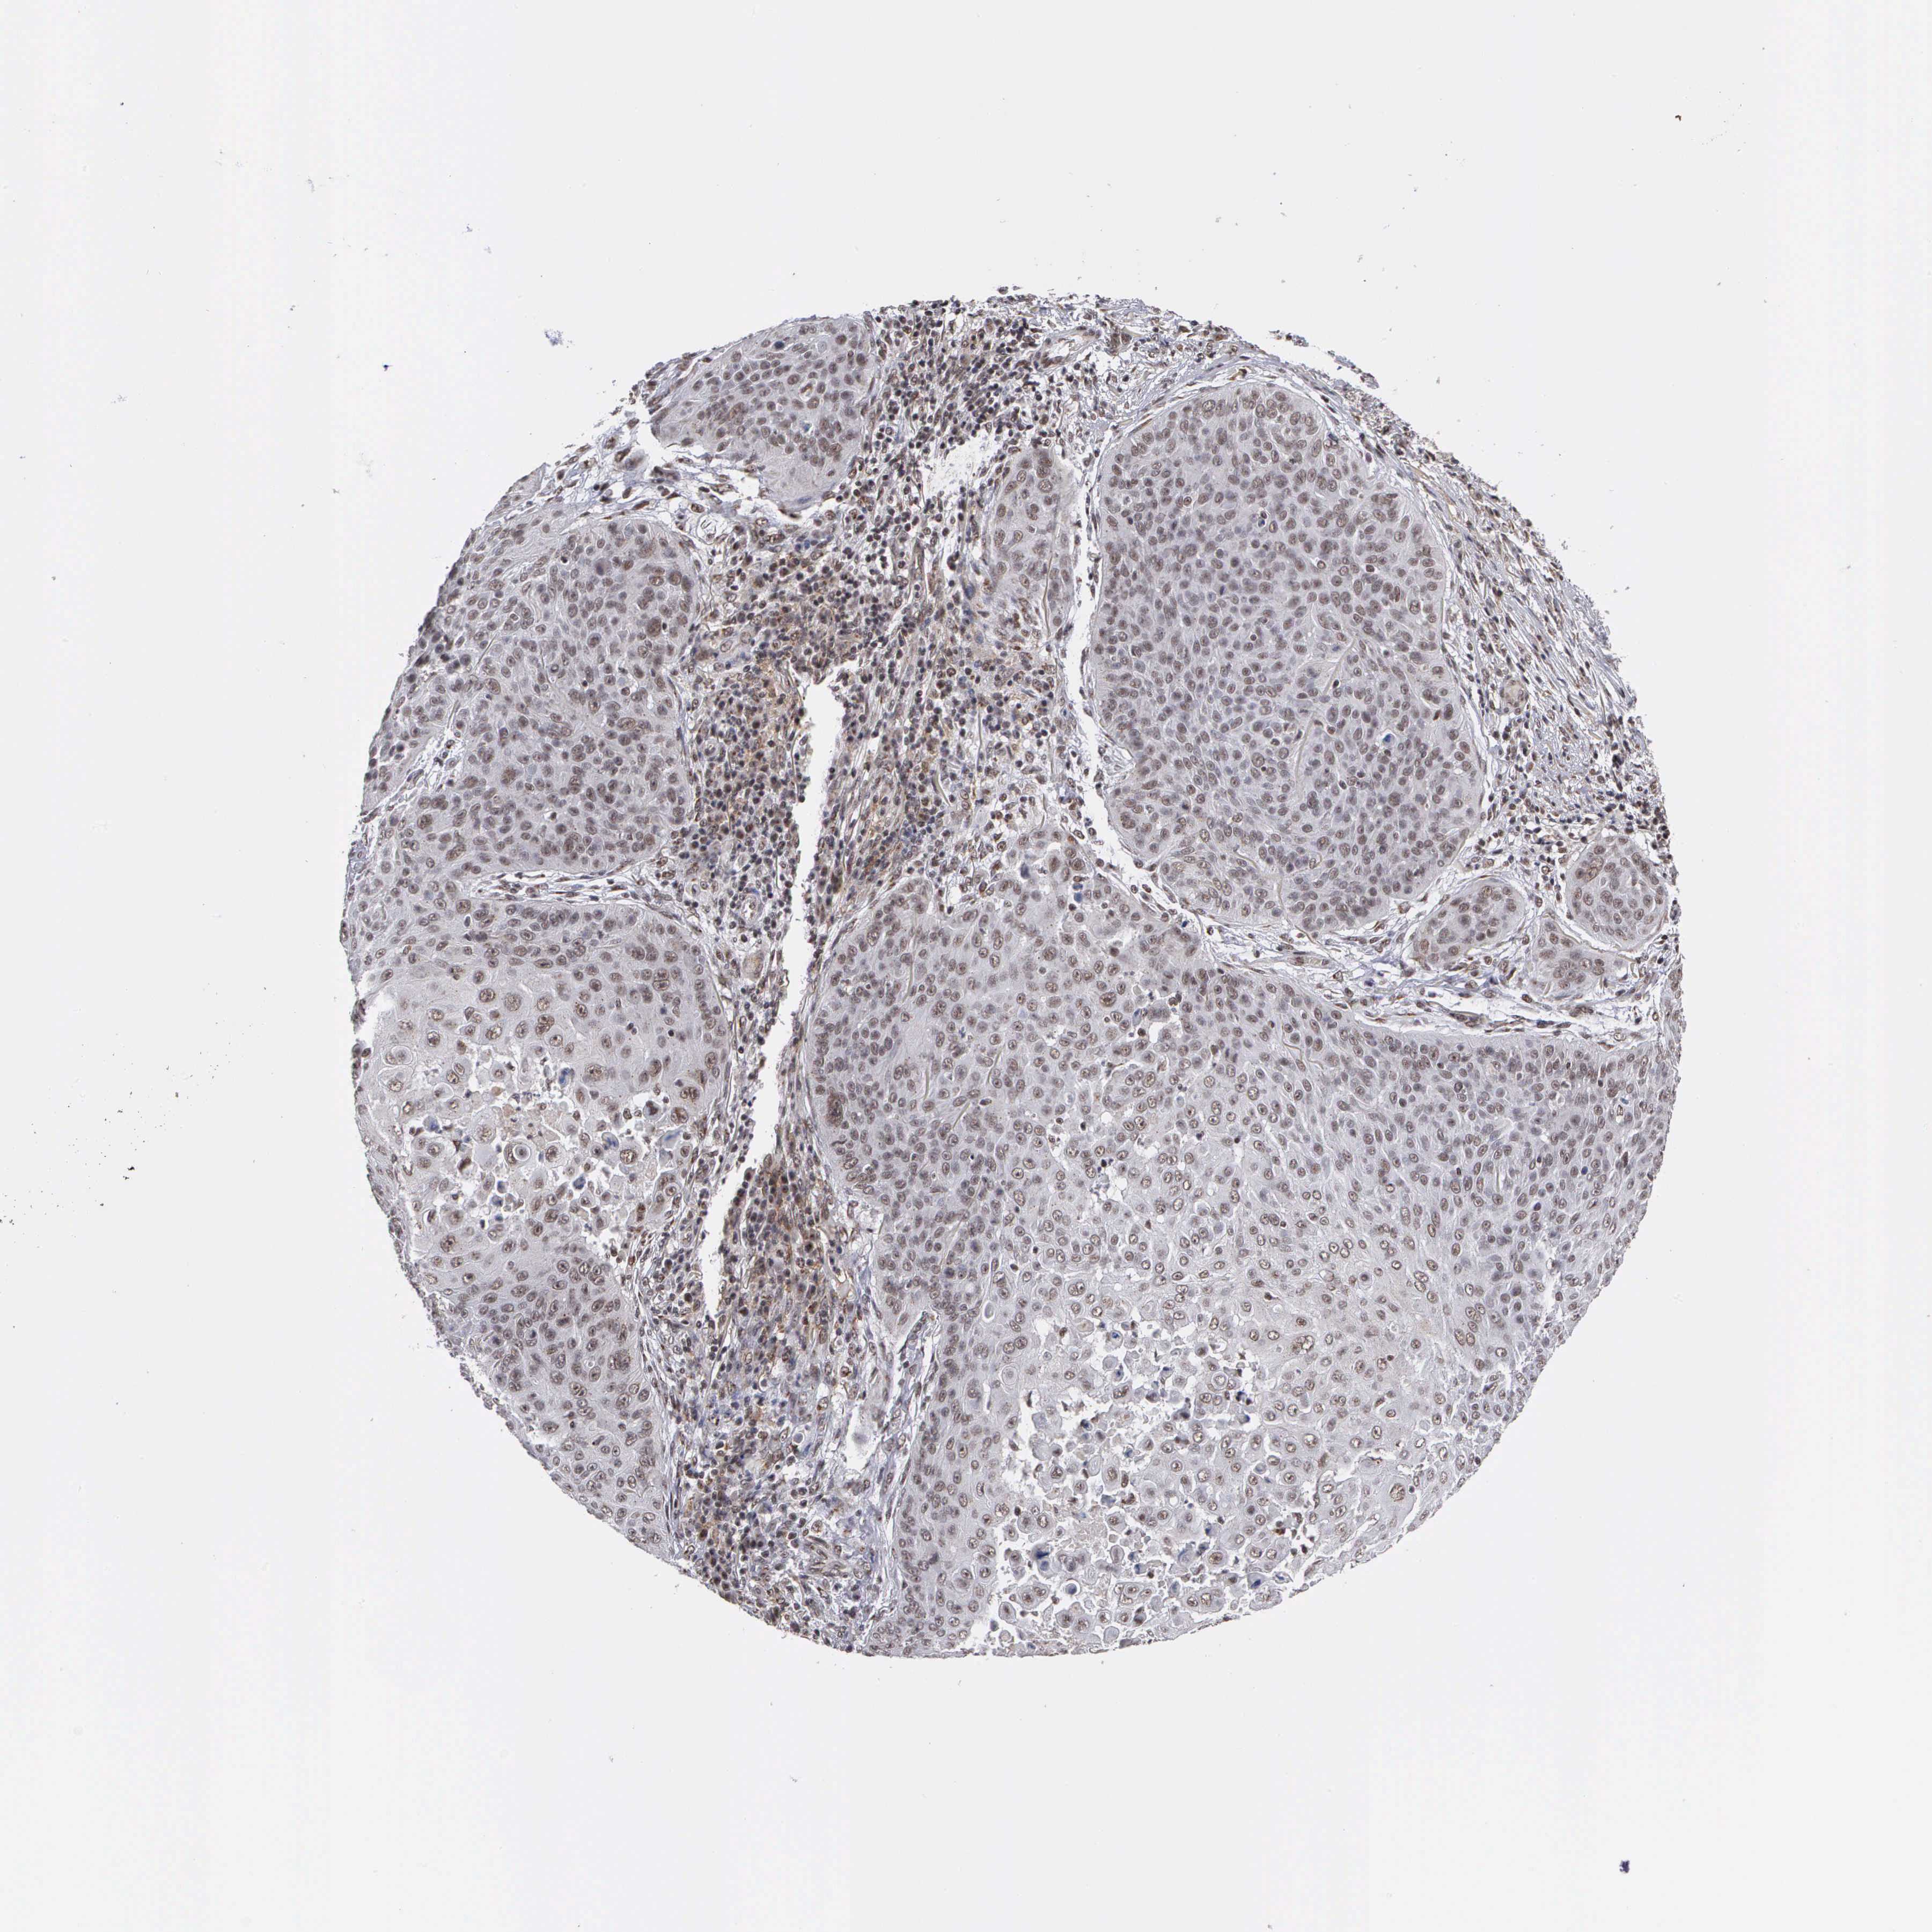

SKIN CANCER - Protein expressioni

A mouse-over function shows sample information and annotation data. Click on an image to view it in a full screen mode. Samples can be filtered based on level of antibody staining by selecting one or several of the following categories: high, medium, low and not detected. The assay and annotation is described here.

Antibody stainingi

Antibody staining in the annotated cell types in the current human tissue is reported as not detected, low, medium, or high, based on conventional immunohistochemistry profiling in selected tissues. This score is based on the combination of the staining intensity and fraction of stained cells.

Each image is clickable and will lead to virtual microscopy that enables deeper exploration of all samples and also displays staining intensity scores, fraction scores and subcellular localization as well as patient and tissue information for each sample.

Antibody HPA000869

Intensity

Strong

Moderate

Weak

Negative

Quantity

>75%

75%-25%

<25%

None

Location

Nuclear

Cytoplasmic/membranous

Cytoplasmic/membranous,nuclear

Squamous cell carcinoma, NOS

Basal cell carcinoma